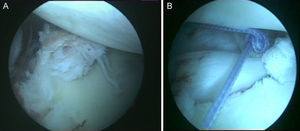

Técnica quirúrgicaBajo anestesia general y locorregional (bloqueo interescalénico), se intenta reducir el hombro de forma cerrada. En caso de no conseguirlo se coloca al paciente en decúbito lateral con tracción de unos 5kg y, siguiendo la técnica descrita por Verma5, se introduce un «Wissinger» por el portal posterior estándar, el que empleamos para la artroscopia de hombro. Con el «Wissinger» a través del portal realizamos tracción de la cabeza humeral hacia lateral, apoyándonos en la cápsula y en la parte posterior del manguito, no en el hueso. Habitualmente con esta maniobra conseguimos introducir la cabeza humeral en la glenoides y podemos pasar a realizar la artroscopia de hombro. En caso de no conseguir una reducción, pasaríamos a realizar una reducción abierta con el paciente en posición de silla de playa y con una vía de abordaje anterior al hombro. Con el hombro reducido se realiza la artroscopia de hombro. Se emplean los portales posterior, anterosuperolateral, anterior, portal de Wilmington y portal posteroinferior. Se estudia la lesión de Hill-Sachs inverso, la relación con el tendón del subescapular y la lesión del labrum posterior (fig. 2, figs. 3 y 4), el resto del labrum y el manguito de los rotadores. Hay que limpiar bien la articulación, extirpar todo el tejido fibroso, liberar el labrum posterior de las adherencias a la glena, preparar el lecho óseo de la glena antes de colocar los implantes (en el caso 1 se emplearon 2 implantes Lupine BR [DePuy Mitek, Raynham, MA], y el caso 2 con un Gryphon BR [DePuy Mitek, Raynham, MA] cargado con doble sutura), realizar la reconstrucción capsulolabral con un pasador directo o indirecto, anudar y cortar las suturas. Una vez reparadas las lesiones soltamos el brazo del sistema de tracción y comprobamos la relación de la cabeza humeral, del defecto óseo anterior con la glenoides, al hacer rotaciones del hombro (sobre todo si hay riesgo de «enganche» con la rotación interna), y decidimos si fijamos el tendón del subescapular en el defecto óseo humeral anterior, tal y como describió Krackhardt6.

No es estrictamente necesario que reproduzcamos un enganche de la lesión de Hill-Sachs inversa para decidir realizar el remplissage inverso. Con la óptica en el portal anterosuperolateral liberamos el tendón del subescapular, su cara anterior y posterior. Preparamos el lecho óseo de la cabeza humeral, extirpando todo el tejido fibroso de la lesión de Hill-Sachs inversa, con el sinoviotomo, la fresa de hueso o periostotomos, hasta obtener hueso sangrante. Entonces desde el portal anterior, insertamos los implante en el defecto óseo (en el caso 1 un 5,5 Healix BR [DePuy Mitek, Raynham, MA] con 2 suturas UHMWPE [Orthocord; DePuy Mitek]) en el tercio superior y en la zona más medial del defecto (fig. 5), y en el caso 2 insertamos 2 Gryphon BR Healix BR (DePuy Mitek, Raynham, MA) con 2 suturas UHMWPE (Orthocord; DePuy Mitek), uno inferior y otro superior en la zona más medial del defecto óseo. Recuperaremos las suturas desde un portal anterosuperior accesorio y con una pinza para atravesar el tendón (Penetratror DePuy Mitek, Raynham, MA) a través del portal anterior, atravesamos el tendón del subescapular y recuperamos las suturas. Daremos puntos colchoneros, uno inferior y otro superior, para conseguir un buen contacto del tendón con el hueso, separando los puntos entre 1 y 2cm (fig. 6). Podemos ayudarnos con un empujanudos a través del portal anterosuperior accesorio para el manejo y recuperación de las suturas, acercándolas a la boca de la pinza penetrator, tratando de no mover en exceso la pinza una vez atravesado el tendón, para evitar lesionar el tendón y el cartílago. Manteniendo el brazo en 35-40° de rotación interna anudamos primero el punto inferior y luego el superior (figs. 7 y 8).

Caso 1, hombro derecho. A. Vista desde el portal ASL de la lesión de Hill-Sachs inversa con el implante en el tercio medial del defecto óseo. B. Imagen después de hacer los nudos; podemos ver el tendón del subescapular rellenando parcialmente el defecto óseo de la cabeza humeral, con la cabeza centrada en la cavidad.

Caso 2, hombro izquierdo. A. Visión desde el portal ASL de la cara posterior del subescapular con los 2 implantes en la parte inferior y superior del defecto óseo. B. Imagen tras el anudado del punto más inferior. C.